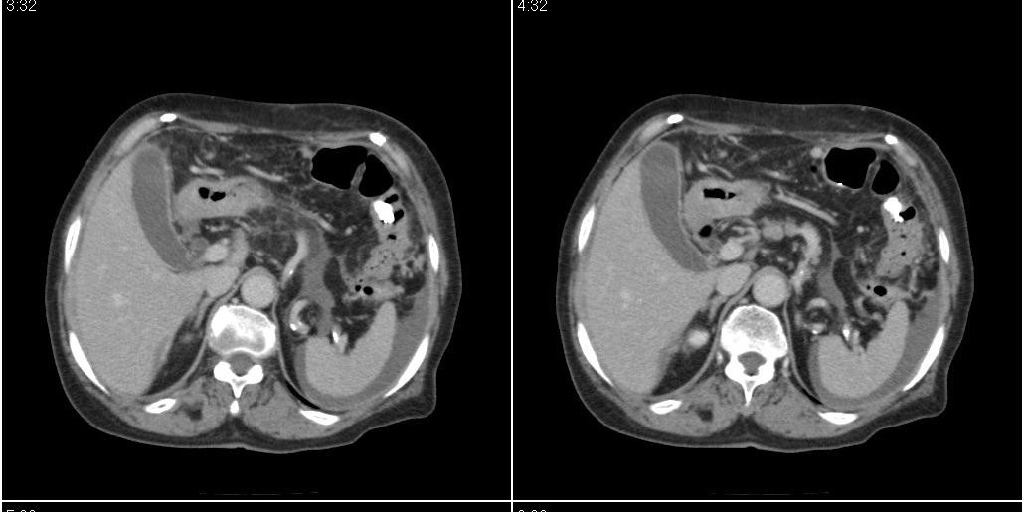

胆囊有问题么,是结石么?胆囊内异常密度平扫30hu左右,增强各期无变化。

胆囊内稍高密度影,无强化,胆囊壁增厚,周围见低密度影,右侧膈肌角及脾周水样密度,支持胆囊泥沙样结石,胆囊炎、胆囊窝积液,胸腹水。